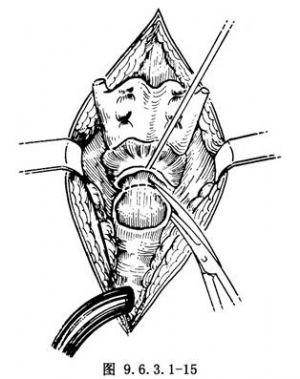

(1)切除喉體:當喉體遊離後,在環狀軟骨下緣橫行切開環氣管韌帶,如保留環狀軟骨,則在環甲膜切開,向後切開環狀軟骨後板(圖9.6.3.1-15)。用組織鉗夾持環狀軟骨向上抬起,鈍性分離環後區軟組織,達杓狀軟骨上緣及兩側梨狀窩的黏膜下層。橫行切開杓間區切跡黏膜,開放喉咽腔即可窺見會厭,鉗夾會厭尖拉向下。根據病變範圍決定從會厭前間隙切開,連同舌骨體一併切除,或保留舌骨從甲狀舌骨膜切開進入喉咽腔,將此切口與杓間切跡切口相接,即可切除喉體。